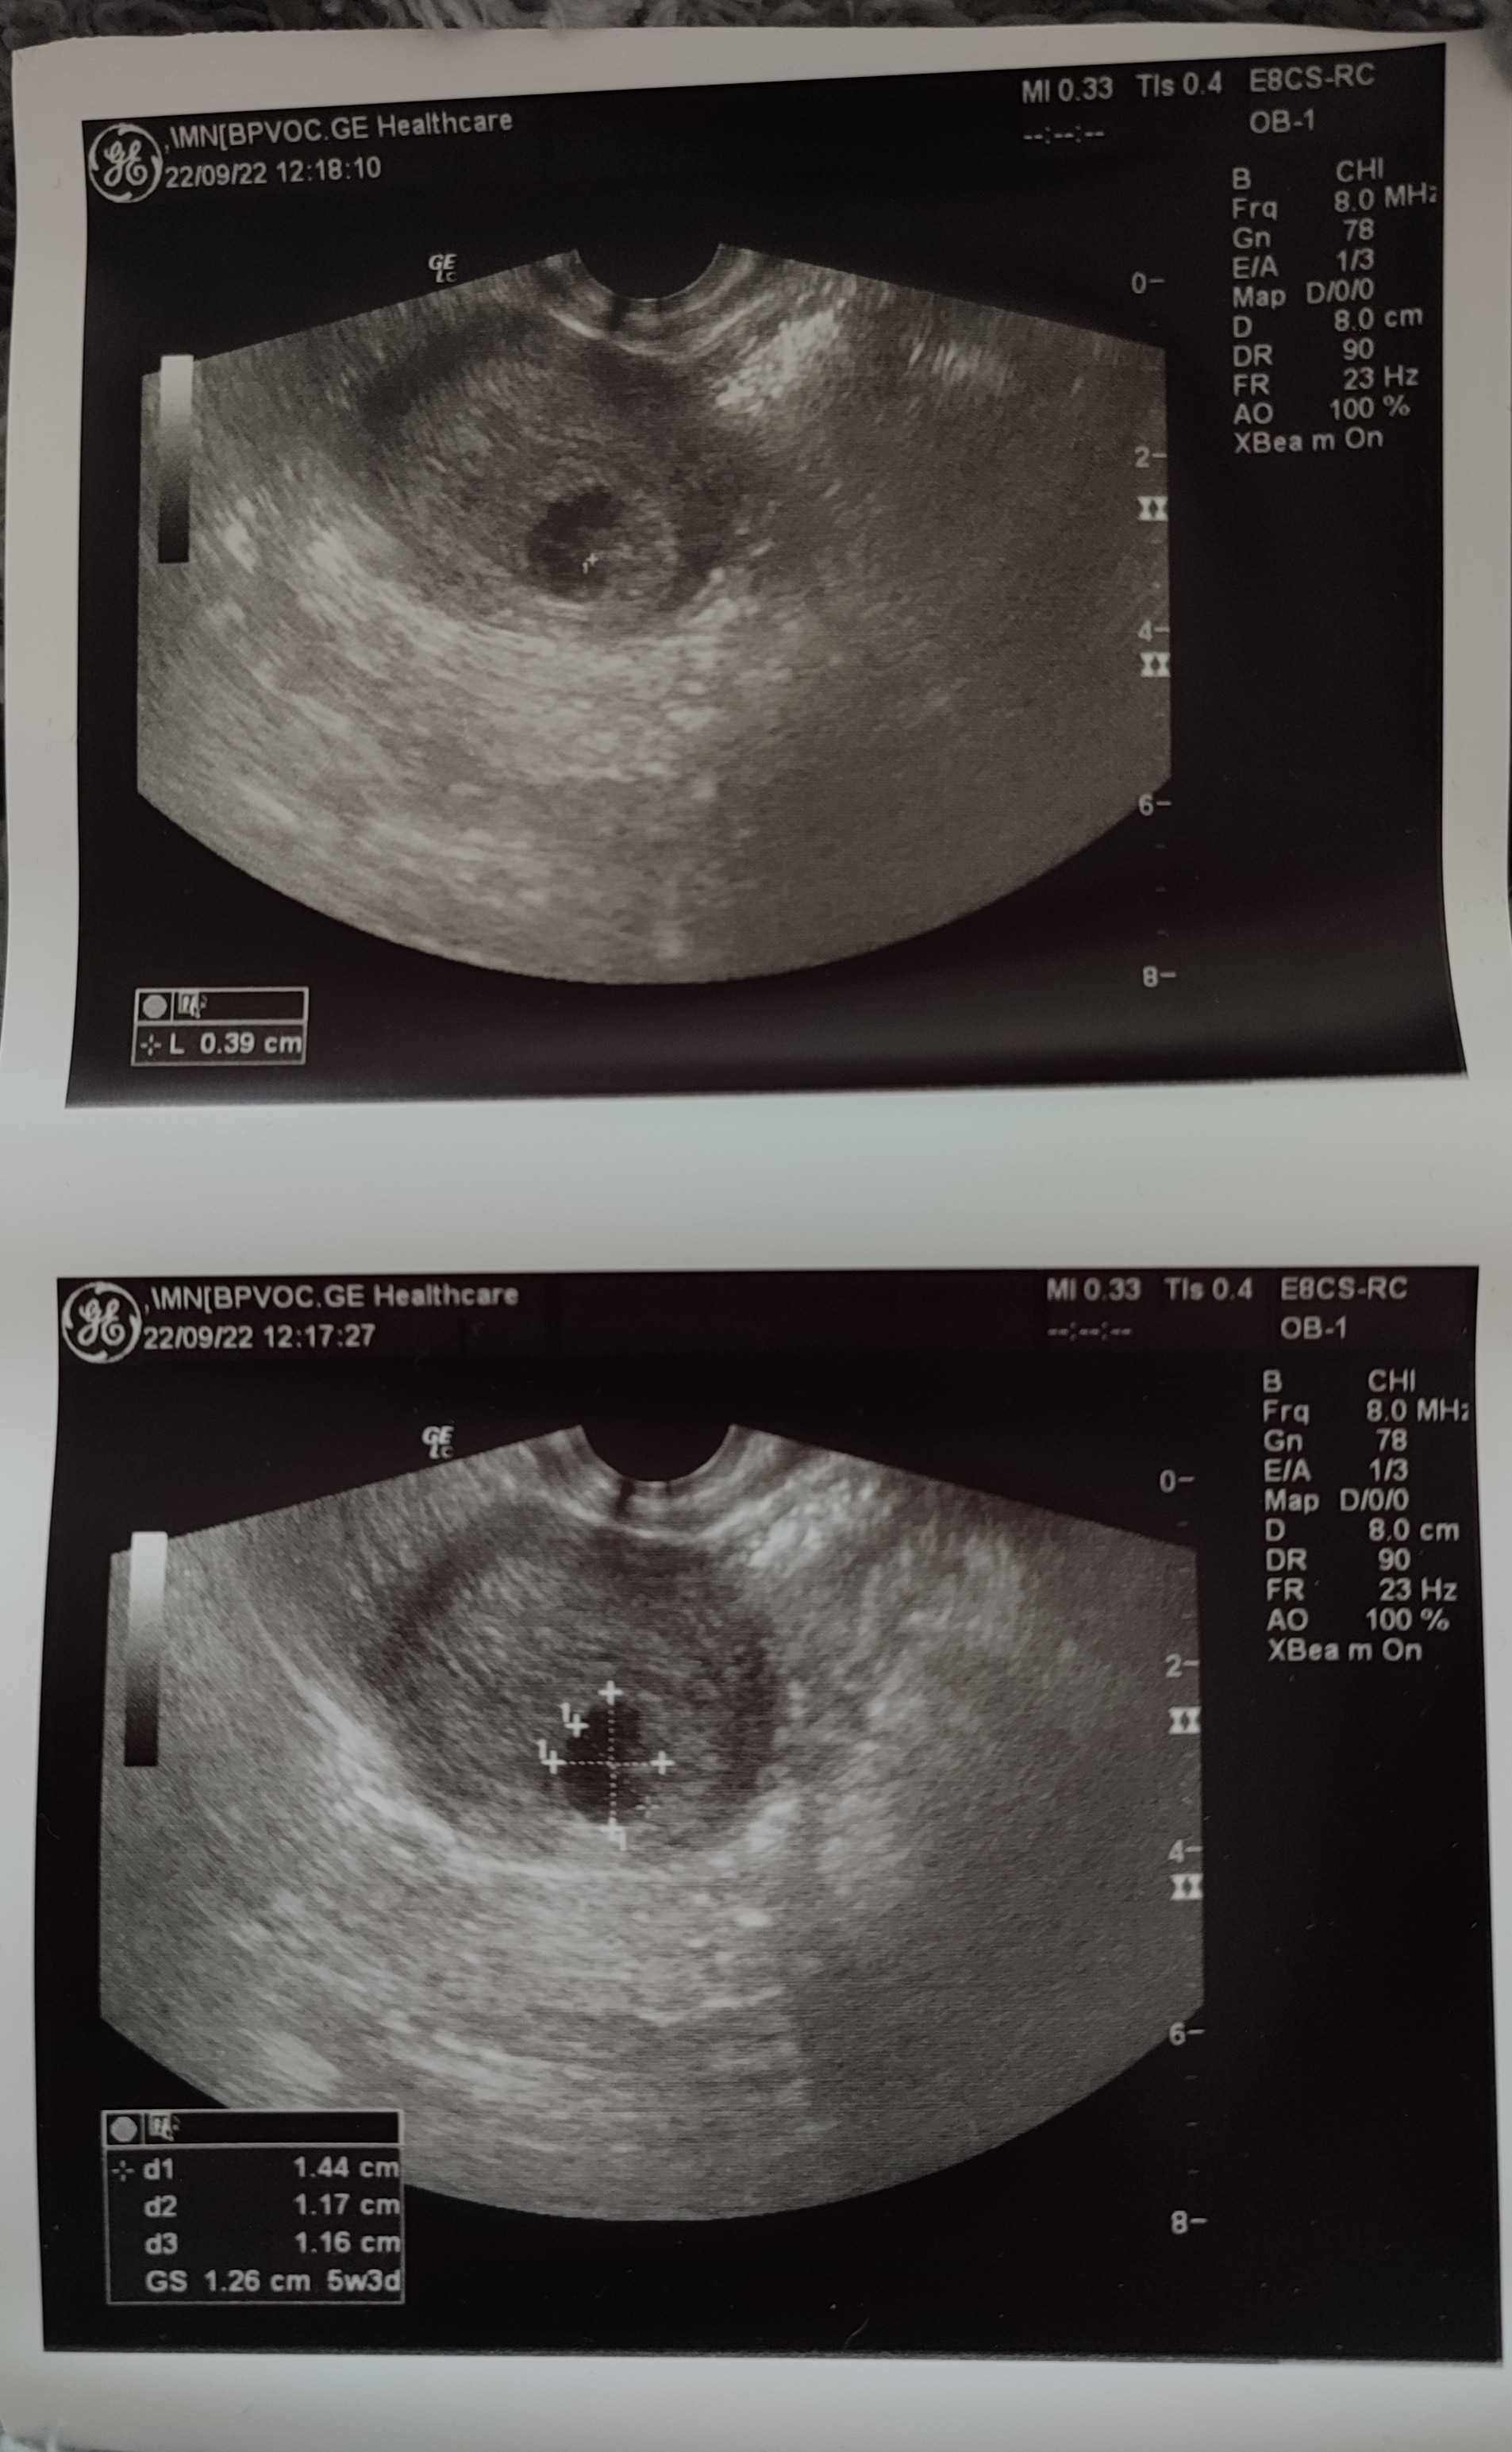

Dziewczyny, byłam wczoraj na 1 USG. Wg OM z aplikacji miałam 6+3, natomiast lekarz stwierdził 5+3 według wielkości pęcherzyka ciążowego. Potwierdził ciążę i powiedział, żeby przyjść za tydzień bo póki co, jest za wcześnie na serduszko.

Dostałam zdjęcie ale ja kij co tam widzę

, może jakiś szajski sprzęt miał, czy ja już świruje?

Zobacz załącznik 1446066